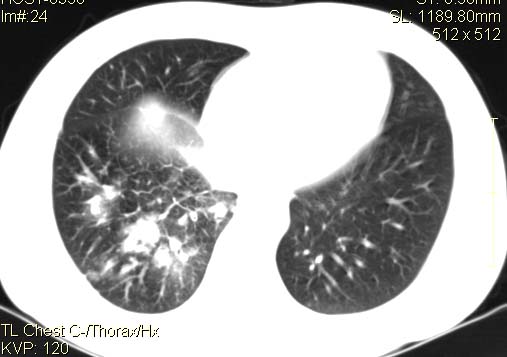

以下是引用qc80012345在2007-4-17 12:33:00的发言:[br]右肺下叶周围型肺癌伴肺门及纵隔内淋巴结转移;比较清楚。

以下是引用qingyuan在2007-4-17 14:19:00的发言:[br]右肺下叶外侧后段胸膜下区节结样病变、分叶、内可见空洞,壁厚薄不均,胸膜凹陷、肺门周围区纹理增粗、僵硬、并近似小结节样改变,肺门区软组织节结、纵膈淋巴结肿大,患者病史长、抗炎治疗无好转炎性改变基本排除,考虑:右肺下叶周围型肺癌伴纵膈及右肺门区淋巴结转移、肺内淋巴管受侵。